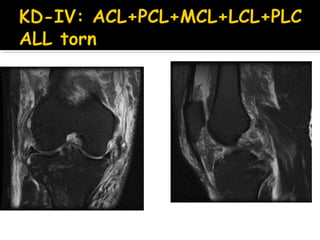

KD IV - Panligament rupture.

WORSE outcome in KD-IV (all 4

KD I -Multiligamentous rupture with either cruciate intact. KD II - Bicruciate rupture with both collaterals intact (rare(. KD IIIM - Bicruciate and medial collateral ligament (MCL( rupture. KD IIIL - Bicruciate and lateral collateral ligament (LCL( rupture. KD IV - Panligament rupture. KD V - Knee dislocation with periarticular fracture C (added to above( - Arterial injury included N (added to above( - Nerve injury included

85 patients, 2-9yrs f/u No difference acute vs. chronic surgery WORSE outcome in HIGH energy WORSE outcome in KD-IV (all 4 ligaments Injured) Selective arteriography based on serial exam is SAFE 87% grade II-IV arthritis compared to 36% on uninjured side Engebretsen L 2009Engebretsen L 2009